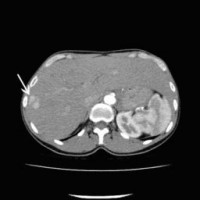

Computertomographische Darstellung eines hepatozellulären Karzinoms (Pfeil)

(Bild 1 von 5)

Computertomographische Dokumentation der Embolisateinlagerung innerhalb des Tumors nach transarterieller Chemoembolisation (TACE)

(Bild 2 von 5)